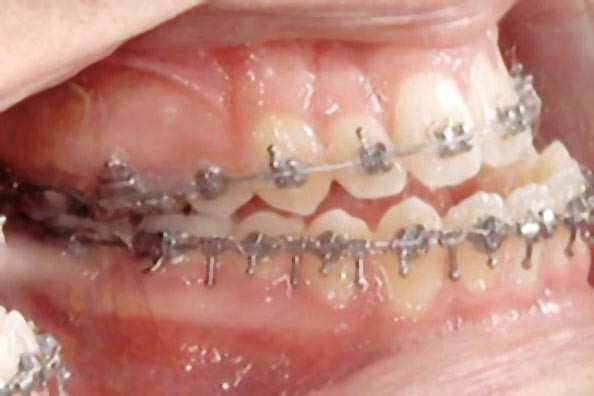

Une pause thérapeutique est ensuite entamée jusqu’à la fin de croissance soit 18 ans. Une poursuite du traitement par préparation secondaire à la chirurgie orthognathique bimaxillaire est programmée.

Les mouvements de décompensations sagittales et transversales sont réalisés à l’aide des tractions inter-arcades. La réévaluation céphalométrique et l’analyse des moulages confirment l’indication d’une chirurgie maxillaire de propulsion et d’une chirurgie mandibulaire par clivage bilatéral des branches montantes pour un recul mandibulaire modéré accompagné d’une génioplastie bidimensionnelle élargie qui rappelle la technique de Chin Wing.